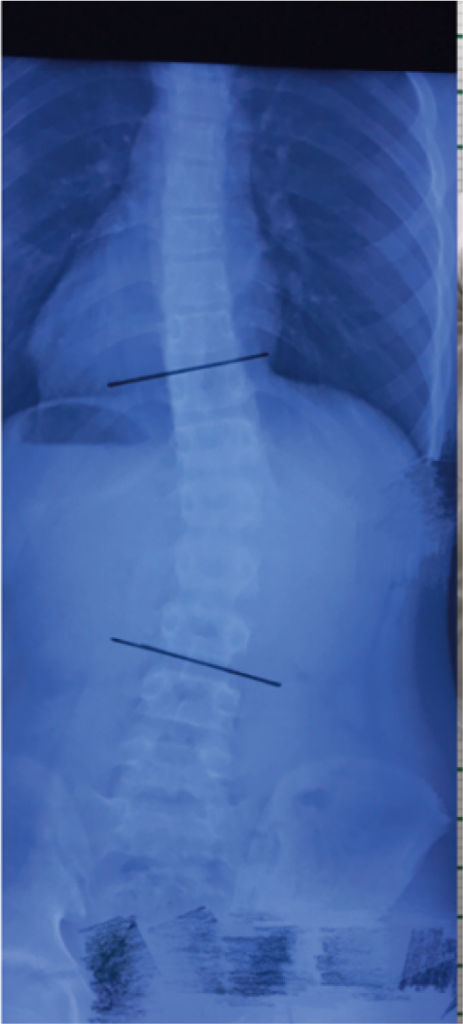

3D-сканирование для сколиоза

Сколиоз – это боковое искривление позвоночника, при котором позвоночный столб принимает форму латинской буквы S. Это отличает сколиоз от искривления назад (кифоза), и искривления вперед (лордоза).

Формирование и прогрессирование такой сложной патологии позвоночного столба неизбежно влечет за собой деформацию грудной клетки, нарушение правильного взаиморасположения органов грудной и брюшной полости, а также приводит к функциональным нарушениям многих систем организма. Помимо этого сколиоз сопровождается выраженным косметическим недостатком.

Для лечения сколиоза применяют консервативные и оперативные методы. Консервативное лечение направлено на предотвращение вторичной патологии внутренних органов и обеспечение профилактики ранних дегенеративных изменений позвоночного столба. Для этого с помощью рентгенографии и индивидуального корсета корректируют и стабилизируют искривленный позвоночник.

Изготовление ортеза корсета требует индивидуального подхода. Ортез корсета должен подходить к форме тела и соответствовать точкам давления деформации позвоночника. Комфорт пациента также играет важную роль, так как корсет носится в течение длительного периода. А 3D-сканер помогает упрощать процесс индивидуального проектирования и одновременно предоставлять удобный опыт использования.

Традиционное производство ортопедических изделий основано на создании гипсовых форм, последующем литье и полировке, что часто приводит к неточностям и дискомфорту пациента.

Цифровой рабочий процесс

Сканирование. Использование EinScan H2 для получения высокоточных 3D-данных о контурах тела, которые служат основой для дизайна.

Дизайн. Сочетая данные 3D-сканирования с компьютерной томографией, врачи диагностируют тип сколиоза, а ортопеды разрабатывают индивидуальный ортопедический план на основе диагноза, создавая 3D-модель ортеза.

3D-печать. Индивидуальный ортез печатается на 3D-принтере, что обеспечивает точное соответствие форме тела пациента.

Цифровой 3D-ортез позвоночника

Проблема: Традиционное производство спинальных ортезов основывалось на гипсовых формах, что приводило к неточностям и дискомфорту. Сам процесс занимал много времени, а готовые ортезы получались тяжелыми и неудобными. Из-за этого пациенты часто отказывались их носить.

Решение: В студии сколиоза Mei Zhao ортопеды используют сканер EinScan H2 для получения точных 3D-данных о торсе пациентов. После 3D-сканирования проводится 3D-моделирование и разработка индивидуальных ортезов для позвоночника с оптимальной посадкой. Затем ортезы печатаются на 3D-принтере с использованием легких, дышащих материалов для лечения сколиоза.